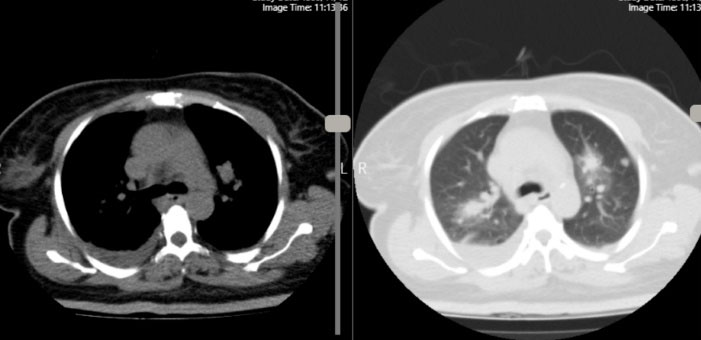

She had a history of COVID-19 infection two month ago, with presentation of myalgia, fever and cough confirmed by positive nasopharyngeal swab test Polymerase Chain Reaction (PCR). Therefore, received supportive care at home quarantine for two weeks and didn’t experienced dyspnea or hypoxemia. In her chest Computed Tomography (CT) performed at that time, there was just faint patchy ground glass opacity in lingula and left lower lobe that could be due to COVID-19 infection. Her symptoms improved but 2 weeks after recovery, she developed acute unset of dyspnea which pulmonary thromboembolism was diagnosed in her work up (Figure 1, Supplementary Files, Video 1-3). She underwent anticoagulation therapy and was relatively good until 10 days before, which became febrile, associated with lethargy and loss of appetite and in outpatient visit. Then, antibiotic was prescribed for her but the fever persisted and she developed dyspnea. She also had a history of Diabetes Mellitus (DM), Hypertension (HTN) and hypothyroidism being on oral medication.

Figure 1.

chest CT angiography that showed filling defects in sub segmental branches of basal segment of both pulmonary arteries (left side here) in favor of pulmonary emboli associated with sub segmental collapse consolidation in base of both lungs